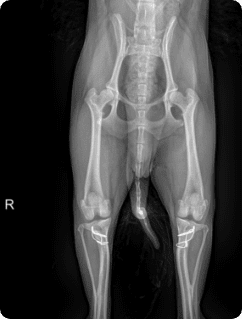

골절, 골종양 등

일산시티동물의료센터 방사선(X-ray) 검사는 탁월한 영상품질로 세밀하고 선명한 영상을 얻을 수 있습니다.